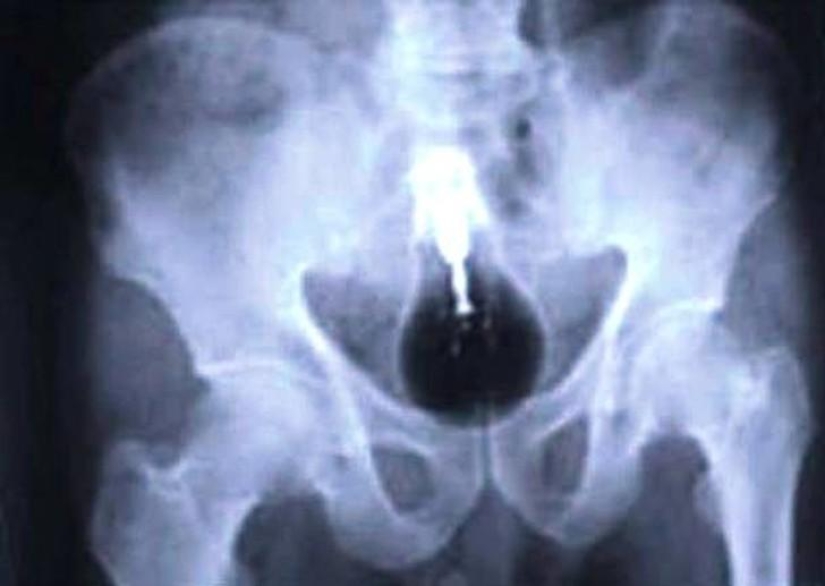

Bala.